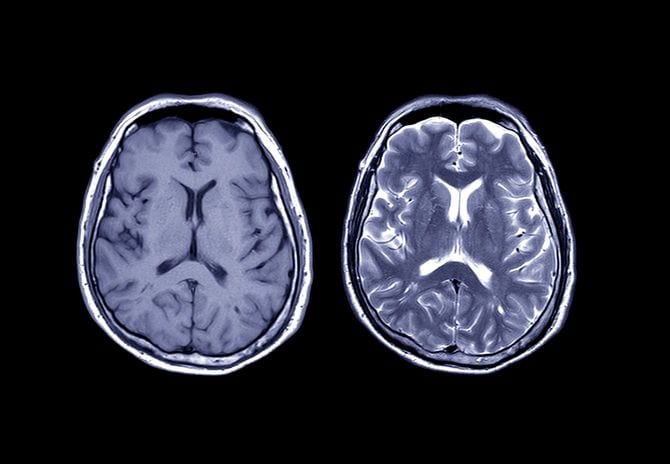

「頭部のCTで、前頭葉に脳腫瘍のような影がみつかりました。MRIを撮ってみないと詳しいことはわかりませんので、検査入院していただけますか」

ということがわかる。やがてMRIの結果が出た。

「悪性の脳腫瘍でした。しかも悪性度が一番高い、グレード4の神経膠芽腫です」